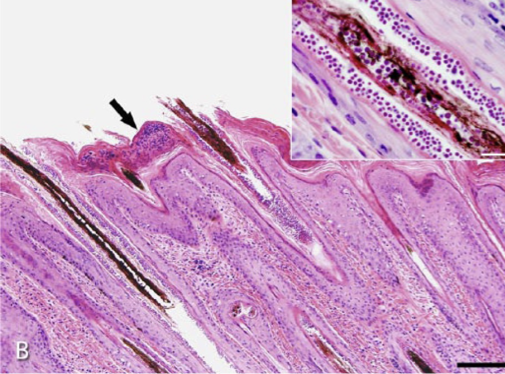

How does dermatophilosis present histologically?

Alternating layers of parakeratotic and orthokeratotic keratin

Epidermal (and dermal) mixed inflam cells (mostly neutrophils)

Characteristic intra-epidermal bacteria